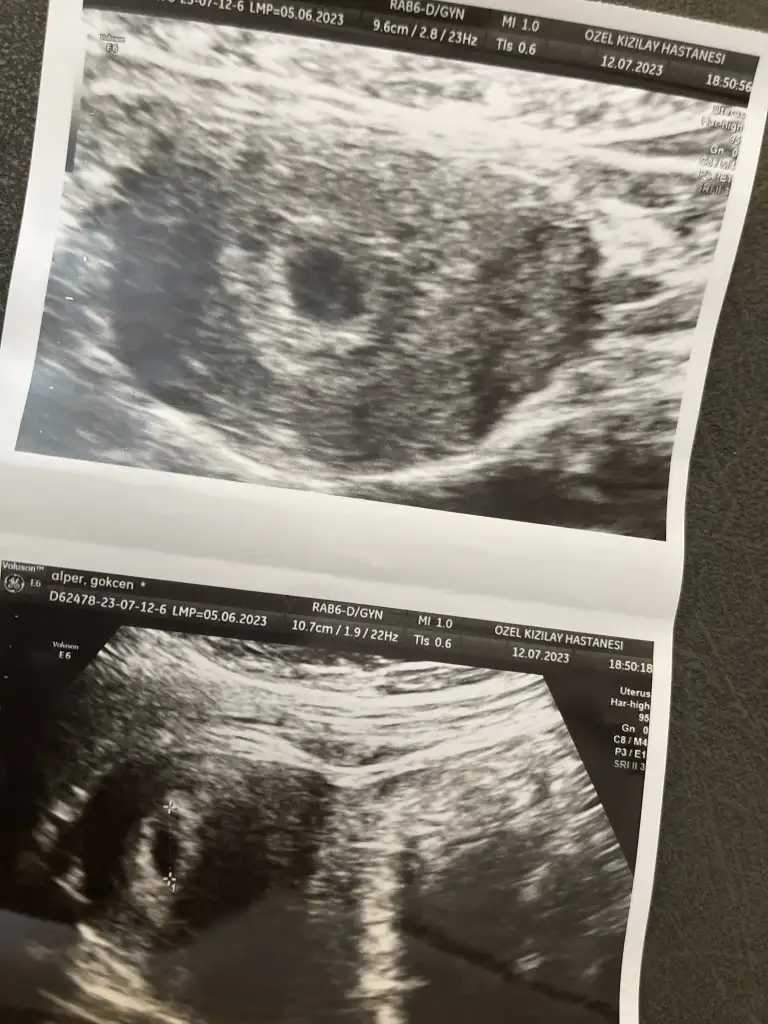

Kızlar ben bugün başka bi doktora gittim . Beta hcg nin 4 günde 10 kat artması konusunda biraz olumsuz konuştu . Down sendromu ya da sağlıksız gebelik de olabilir dedi . Ama karından keseye baktı şimdilik normal gözüküyor bişey deyemeyiz takip edeceğiz dedi. Haftaya gel kalp atışına bakalım dedi . Kese bugün daha netti 1.15 cm miş bu da fotosu . İnşallah sağlıklı olur ya çok korkuyorum :(

Kızlar ben bugün başka bi doktora gittim . Beta hcg nin 4 günde 10 kat artması konusunda biraz olumsuz konuştu . Down sendromu ya da sağlıksız gebelik de olabilir dedi . Ama karından keseye baktı şimdilik normal gözüküyor bişey deyemeyiz takip edeceğiz dedi. Haftaya gel kalp atışına bakalım dedi . Kese bugün daha netti 1.15 cm miş bu da fotosu . İnşallah sağlıklı olur ya çok korkuyorum :KK43: